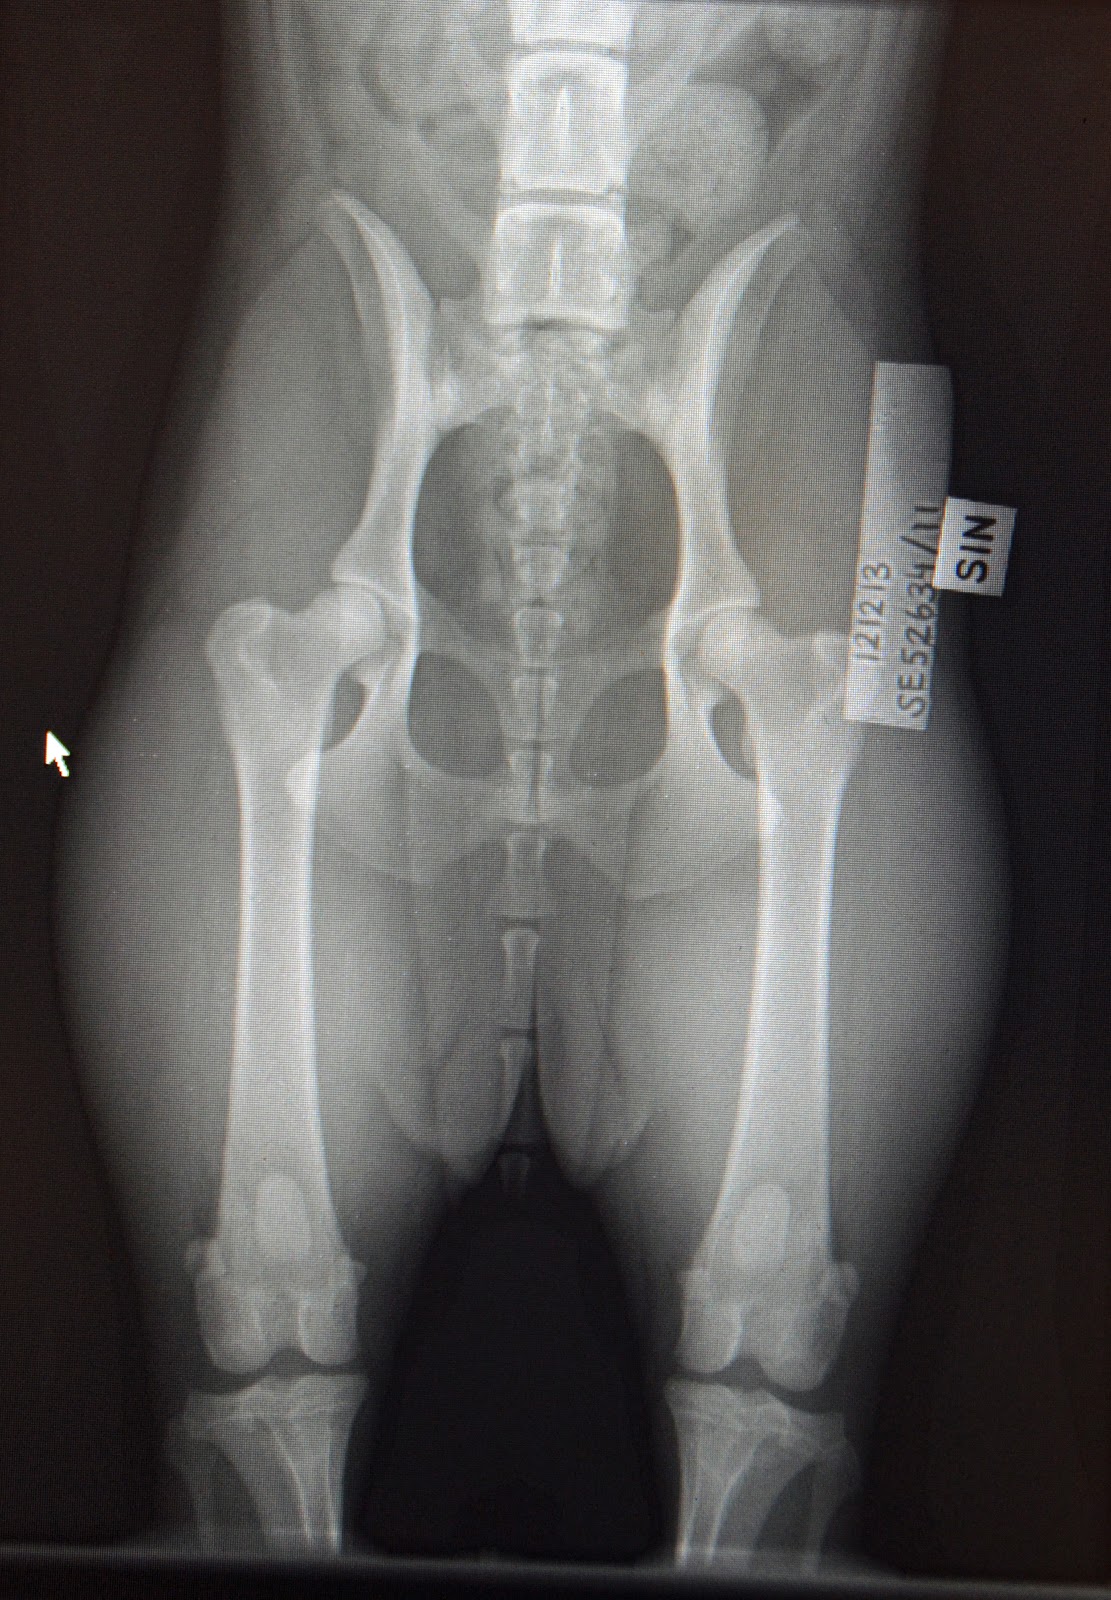

Röntgen gick bra men nu är det en nervös väntan tills resultatet kommer ut på SKK. Så här såg höfterna och armbågarna ut...